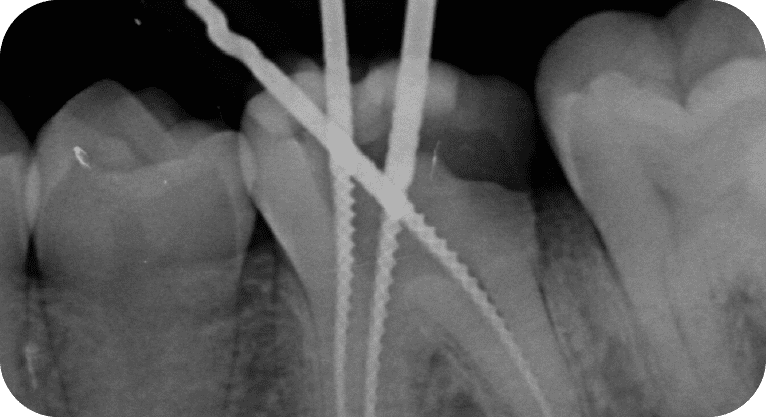

Paciente masculino, “25” años

Tratamiento: Tratamiento de conducto

El paciente presentaba dolor en dos molares por caries profundas. Se realizó endodoncia en ambas piezas, desinfectando y sellando los conductos, seguido de coronas de zirconio para restaurar su función.